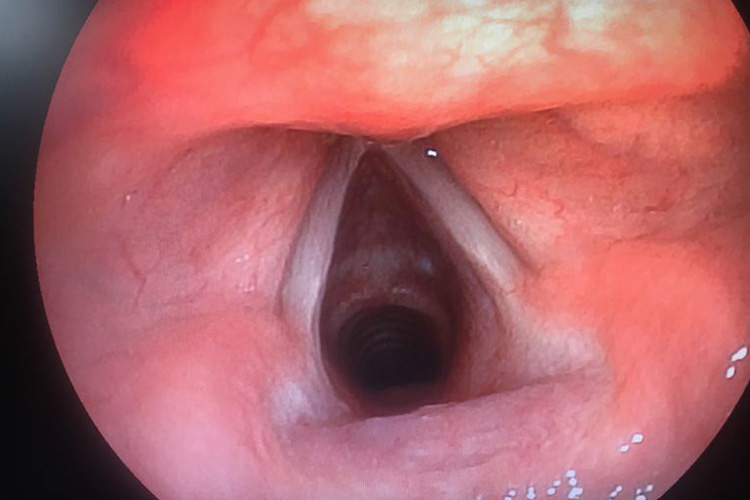

小孩正常喉咙是由喉软骨、韧带、纤维膜、喉肌和喉黏膜等共同构成的管腔。喉腔上起自喉口,与咽相通,向下经气管通支气管和肺。喉腔侧壁有上、下两对黏膜皱襞,上方的一对称前庭襞,下方的一对称声襞。上述两对皱襞将喉腔分为3部分,即前庭襞上方的喉前庭、声襞下方的声门下腔、前庭襞和声襞之间的喉中间腔。

喉咙发炎一般是喉炎,如行间接喉镜检查,可见喉部黏膜充血、肿胀。声带由白色变为粉红色或红色,有时可见黏脓性分泌物附着。声门下黏膜因肿胀而向中间隆起。会出现声嘶、咳嗽、呼吸困难等症状。